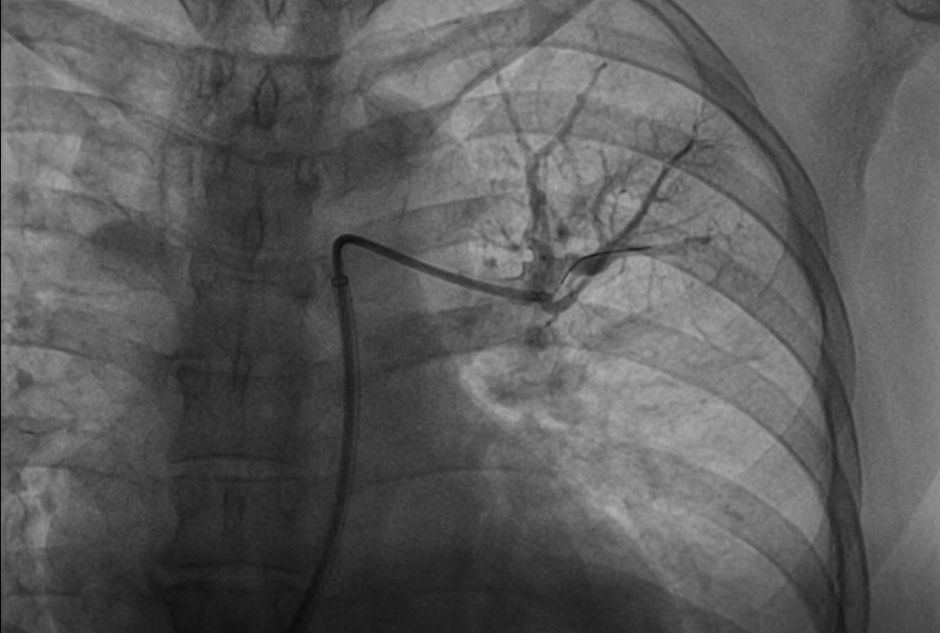

患者慕名至我院后,我科专家进一步对其进行了相关检查,最终诊断为:慢性血栓栓塞性肺动脉高压。心内科周亚峰副院长、陈弹主任、赵良平主任及团队成员进行深入讨论,并邀请呼吸科、血管外科与介入科等进行多学科(MDT)会诊,最终决定对其进行右心导管及肺动脉造影检查,结果提示肺动脉收缩压52mmHg,平均肺动脉压33mmHg,左右各肺动脉及其分支多发栓塞,可见多处血栓影及马赛克征。对右肺动脉A3、左肺动脉A1+2、左肺动脉A9行球囊扩张术,扩张后复查造影远端血流恢复良好。手术后患者的症状得到明显改善,心功能逐渐恢复,住院5天后平稳出院。出院后患者继续进行家庭氧疗、抗凝、利奥西呱降肺动脉压力等治疗,并密切随访中。随访至今,患者情况良好。

扩张后